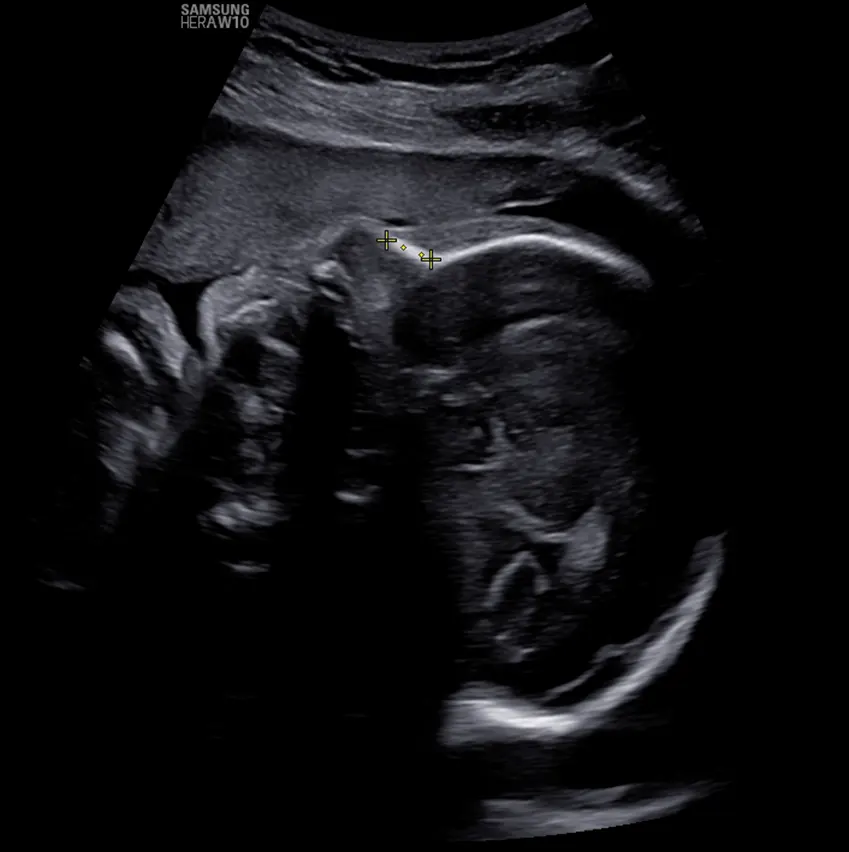

UN DULCE MILAGRO VIENE EN

CAMINO, ACOMPÁÑANOS A

CELEBRAR LA LLEGADA DE

NUESTRO PEQUEÑO TYLER dino gif